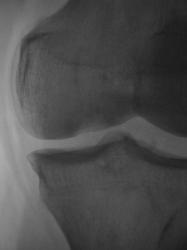

Пациент, врачом хирургом, направлен на рентгенографию коленного сустава в связи с болями. Пациент отмечает, что боли ощущает в течение уже 2-х лет. Ранее производилась рентгенография коленного сустава, однако патологических изменений выявлено не было.

А травмы не было? Латеральнее ММВ как будто бы фрагмент костной плотности. Может быть, болезнь Кёнига? С медиальной стороны щель сустава значительно уже, там же - участок разрежения в мыщелке бедра. На новообразование на первый взгляд не похоже. Без КТ мне трудно судить

Поддерживаю предподожение о б-ни Кенига. Хотя и отсутствует отслоившийся фрагмент, но тем не менее.

В протоколе написал - "состояние после перенесенной болезни Кенига". Хорошо дифференцируется "опустевшее ложе".